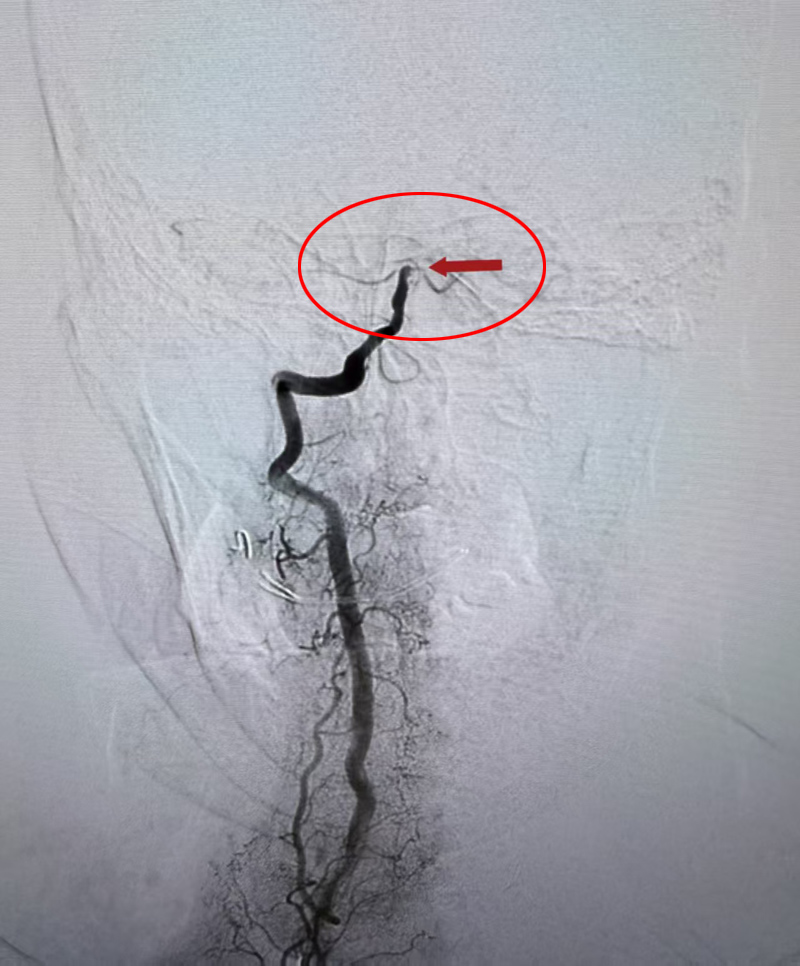

术前

11月2日晚上,60多岁的蒋女士从河北来北京探亲,刚下公交车后感到头晕不适,以为是晕车了就坐在路旁休息,没想到突然失去意识倒在了地上。家属赶紧拨打了急救电话,120急救车立即把蒋女士送到了潞河医院急诊抢救室。急诊神经内科肖淑英主治医师第一时间接诊后,对患者进行了查体,初步判断为急性脑血管病累及脑干,随时会有呼吸衰竭、心跳骤停的风险,情况十分紧急!于是立即启动卒中绿色通道,火速带着患者进行了头颅CT检查,考虑为椎基底动脉系统大动脉急性闭塞。二线值班医生车锋丽主任医师也迅速到达急诊室指挥抢救,同时联系神经介入组做好急诊介入手术准备。就在此时,蒋女士突然出现了血氧饱和度急剧下降,考虑呼吸中枢受累引起了中枢性呼吸衰竭,医生果断为她进行了气管插管接呼吸机辅助机械通气,并一路护送前往导管室进行急诊脑血管造影检查。神经内科副主任程哲带领手术团队已准备就绪,造影检查结果显示患者基底动脉急性闭塞,随即进行了基底动脉取栓手术,仅用时30分钟就成功完成了血管再通。蒋女士即刻恢复了意识,四肢也可以抬起活动了。由于抢救及时,蒋女士术后第二天就顺利拔除了气管插管,言语及四肢活动都恢复至正常状态,术后第五天顺利出院。